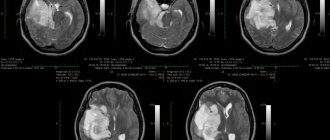

What does a pineal gland cyst look like on CT and MRI?

Computed tomography visualizes a fluid-dense mass with well-defined edges and peripheral calcifications found in 25% of patients. In many cases, there is also a peripheral accumulation of contrast in the cyst in the form of a thin and smooth “rim”. The cyst disrupts the course of the internal veins of the brain, displacing them upward.

Pineal cyst with a typical hyperintense signal on MRI (T2 WI) (marked with a blue arrow). Left: axial tomogram, right – sagittal

The following signs are observed on MRI:

• T1 VI

• Typical iso- or hypointense signal compared to brain parenchyma

• In 55–60% of cases, the signal is hyperintense compared to the cerebrospinal fluid

• The signal is usually uniform

• T2 VI

High intensity signal

• Usually slightly less intense than cerebrospinal fluid

• FLAIR

• High intensity signal that is often not completely suppressed

• DWI/ADC

• There is no diffusion restriction

• T1 WI with contrast enhancement (gadolinium-containing contrast)

Approximately 60% of cysts accumulate contrast

• The accumulation of contrast in most cases occurs in the form of a thin (less than 2 mm) and even “rim” (full or incomplete)

• Diffuse contrast enhancement of the fluid contents of the cyst with gadolinium-based drugs in a delayed phase (60–90 minutes) is possible, as a result of which the cyst becomes similar to a solid space-occupying formation

• Rarely, atypical nodular contrast enhancement may be detected, and signs of hemorrhage into the cyst may also be detected